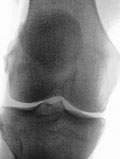

膝关节骨关节炎的临床表现最主要的是膝关节部位的疼痛,常在关节负重时,如上下楼梯时或下蹲起立时膝关节明显疼痛。发病初期,休息后关节疼痛可缓解,但随病情的发展,即使休息时疼痛也较明显,甚至出现跛行,影响日常活动;有些患者出现关节僵硬,如晨起时或久坐起立时出现膝部僵硬,活动后好转。症状加重时,间歇期变短,僵硬时间延长,最后可为持续性。随着病情的进展,有些患者可出现受累关节邻近的肌肉萎缩、关节畸形,最终导致功能障碍。X线表现有:关节间隙变窄,关节边缘出现骨质增生,关节面不规则等,晚期可出现关节畸形。